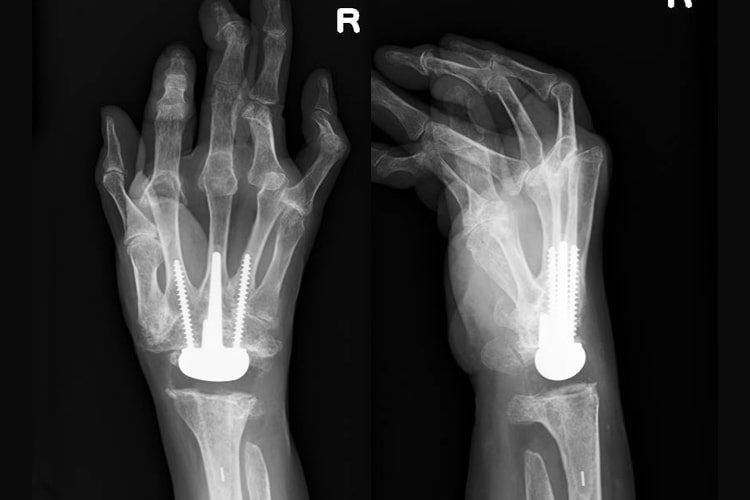

橈骨遠位端骨折

橈骨遠位端骨折写真

術前

橈骨遠位端骨折術後写真

ロッキングプレート固定術後

原因

踏み台やベッドから転倒した際に、手をついて受傷することが多いです。

症状

手首の関節部の痛み、腫れ、変形などが生じます。X線で橈骨(前腕の親指側の骨)の遠位部分に骨折を認めます。大きくズレている場合は手指のしびれが生じることもあります。

治療方針

ほとんどズレがない場合はギプス固定をして治す場合もあります。しかしギプスをしていてもズレてくる危険性が高い場合や関節面がズレている場合は手術が必要となります。手術は専用のプレートを用いて行うことが多いです。